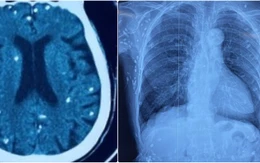

Rùng mình với hình ảnh nang sán dây lợn gây vôi hóa đầy cơ thể

Mặc dù không phát hiện ký sinh trùng sán dây lợn tại thời điểm bệnh nhân nhập viện, nhưng các bác sĩ phát hiện nhiều tổn thương ở não, dưới da vùng bụng ngực, ngực do nang sán dây lợn vôi hóa.